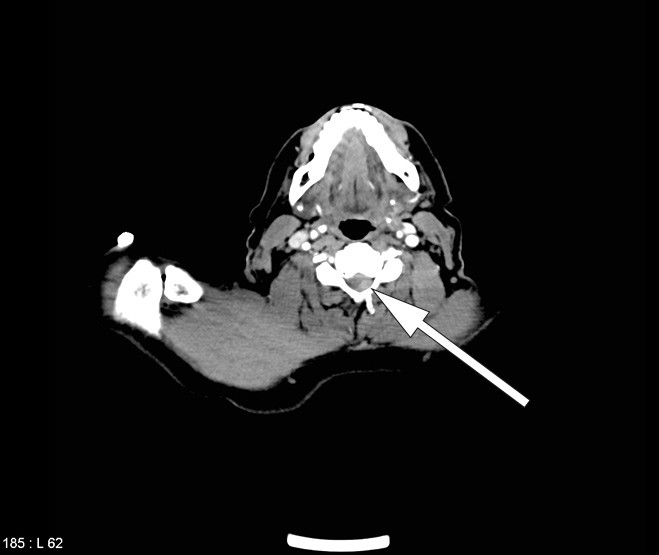

Etter undersøkelse i akuttmottaket ble det i tråd med trombolyseprotokoll utført CT av hjernen med angiografi av halskar og intracerebrale kar. Nativ CT av hjernen var normal, men angiografien avdekket en subtotal stenose i høyre a. subclavia like etter avgangen fra truncus brachio-cephalicus.

CT-undersøkelsen som ble tatt av totalaorta ved innkomst før trombolytisk behandling, ble initialt tolket som normal, foruten en subtotal stenose i a. subclavia. Ved ny gransking av cervikale avsnitt med noe endring av gråtoneskalaen (window/level) fant man imidlertid at epiduralblødningen var synlig allerede før den trombolytiske behandlingen (fig 3).